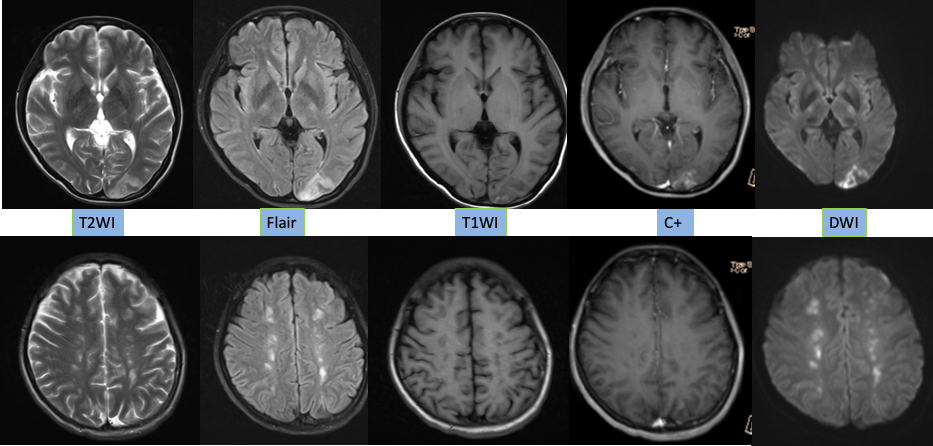

1. 本病例影像学表现提示的诊断线索:青年女性,脑内新见散在多发病灶,散在分布于多个脑动脉供血区,包括幕上幕下,皮层及深部白质,无明显占位效应,病灶周围无水肿,弥散受限,增强扫描左枕叶较大病灶不均匀强化,余病灶无明显强化。

定性诊断:本病例特点为青年女性,有明确肺癌病史,无明确神经系统症状,CT 发现颅内新发多发病灶,结合病史首先不除外转移瘤,MR 进一步检查病灶符合多发急性期脑梗死,确诊脑梗死不难,难的是确认脑梗死的发病原因。

典型影像学表现:DWI 上病灶累及 3 个或 3 个以上血管分布区,常累及前后循环,双侧多见。排除其他明确的栓塞源或与这些病变相关的其他疾病。